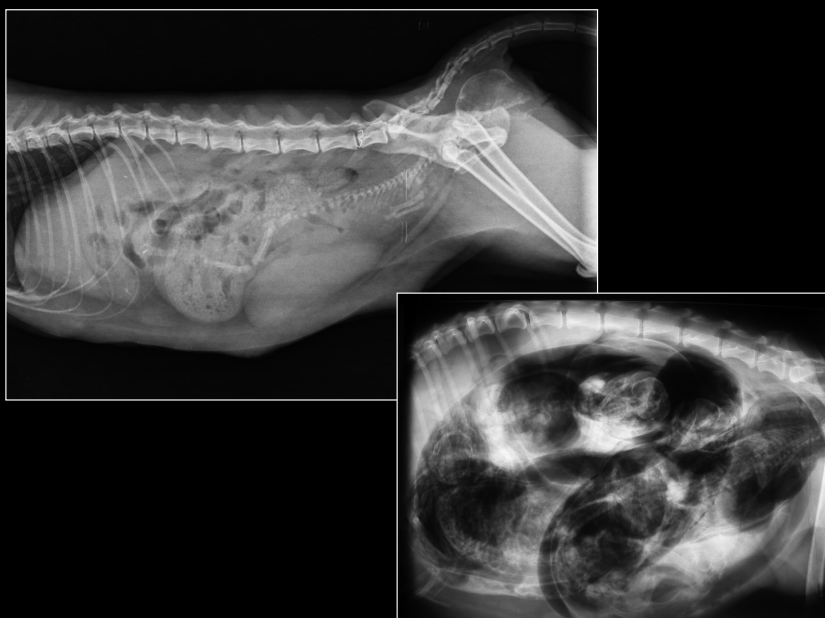

ÚTERO

- Visible cuando distendido: estructuras tubulares tortuosas en abdomen caudoventral.

- Causas:

- Fisiológico: gestación temprana

- Patológico: piómetra, hidrómetra, mucómetra, neoplasia, absceso de muñón

- Gestación: mineralización fetal visible 40–45 días.

- Muerte fetal (Si encontramos gas con los fetos), momificación, distocia (Problemas para el parto).